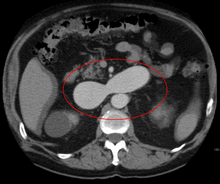

AVMs can occur in various parts of the body:

- liver[10]